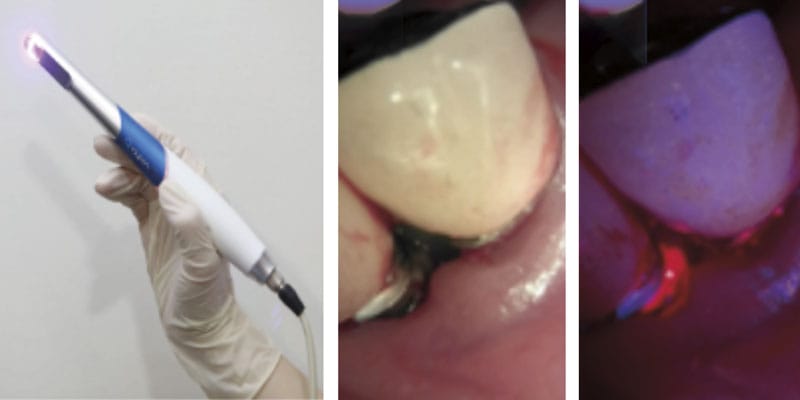

To beat these limitations, biofluorescence imaging programs (BIS), resembling quantitative light-induced fluorescence (QLF), have not too long ago gained consideration as revolutionary alternate options.5 QLF makes use of blue seen mild at a selected wavelength (405 nm) to detect purple fluorescence emitted by porphyrins produced by mature bacterial colonies, permitting for the quantitative evaluation of biofilm location and maturity (Determine 1).6 This real-time visualization allows speedy analysis of biofilm elimination from the implant floor, in the end enhancing remedy precision.6,7

In these case experiences, we current a medical instances during which QLF (Qraypen C, AIOBIO, Seoul, South Korea; Determine 2) was used to evaluate biofilm accumulation on the implant floor of a affected person with peri-implantitis and to substantiate biofilm elimination throughout surgical/non-surgical remedy. Moreover, medical parameters resembling probing depth, bleeding on probing, and radiographic bone loss have been evaluated to evaluate remedy outcomes. Moreover, we talk about the constraints of this expertise and its potential for future developments. This case highlights the utility of biofluorescence expertise as an efficient and exact instrument for biofilm detection and elimination within the remedy of peri-implantitis.